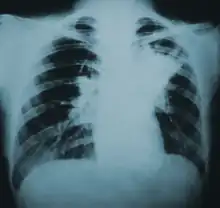

Because the symptoms of blastomycosis resemble those of many other conditions, including tuberculosis and lung cancer, diagnosis is often delayed. In 40% of cases, the diagnosis takes more than a month.[25] A rapid diagnosis can however be made based on microscopic examination of sputum samples or samples obtained from a tissue biopsy or bronchoalveolar lavage.[26]

Once suspected, the diagnosis of blastomycosis can usually be confirmed by demonstration of the characteristic broad based budding organisms in sputum or tissues by KOH prep, cytology, or histology.[27] Tissue biopsy of skin or other organs may be required in order to diagnose extra-pulmonary disease. Blastomycosis is histologically associated with granulomatous nodules.